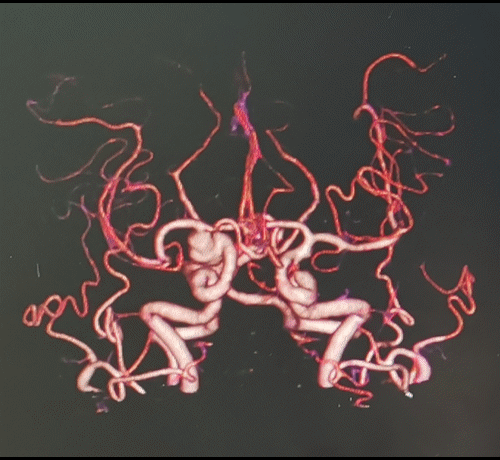

图2 头颅CTA提示右颈内末端动脉瘤,前交通动脉瘤

右颈内动脉交通段以远瘤样扩张,钙化明显,载瘤动脉完全瘤化,局部可见多处小阜突起,无明显瘤颈,最大约16mm╳11mm,前交通囊状动脉瘤约4mm╳3mm,瘤颈约4mm。